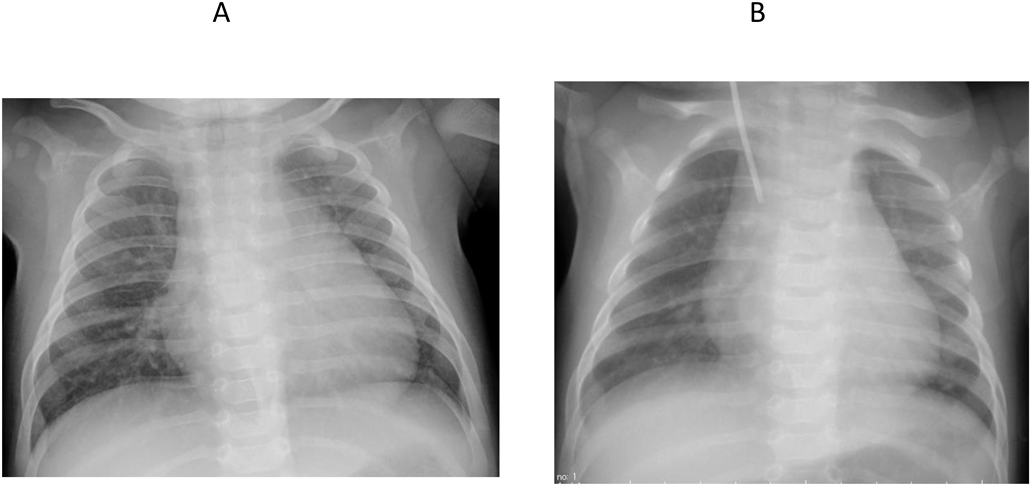

On the operation, a fistula from the superficial femoral artery to the superficial femoral vein was found, and a double ligation was performed (Fig. 3). The patient’s clinical symptoms and NT-proBNP levels improved immediately after the surgery (1,804 pg/mL), and cardiothoracic ratio on chest radiography improved (Fig. 4). She was discharged from the hospital on 84 days of life. She has been well without any symptoms and arteriovenous shunt including recurrence of left femoral fistula has not been observed.

Journal of Pediatric Cardiology and Cardiac Surgery 5(2): 109-112 (2021)

Fig. 4 Chest X-ray

A: CTR showed 61.2% before the operation (75 days of life). B: CTR showed 56.0% after the operation (79 days of life).